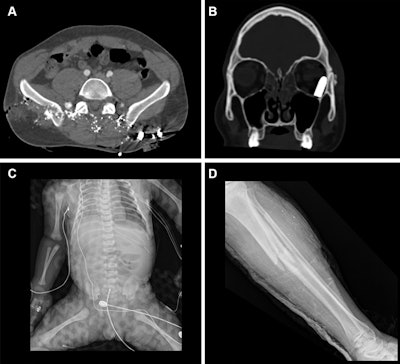

Representative injuries in patients from the mass casualty incident of October 7, 2023. (A) Axial CT scan at the pelvic level in a 34-year-old male patient shows multiple shrapnel fragments in the pelvis, resulting in fractures of the pelvic bones and lumbar vertebrae (not visible on this image). (B) Coronal reconstruction of a head CT scan in a 20-year-old male patient shows penetrating trauma to the left eyeball with a retained bullet in the orbital cavity. (C) Radiograph of a fetus delivered by emergency cesarean section

from a critically injured mother shows a left pneumothorax and catheter in place. (D) Radiograph in a 25-year-old female patient shows a comminuted fracture in the tibial metaphysis with fragment displacement and multiple bony fragments in the surrounding soft tissues.RSNA